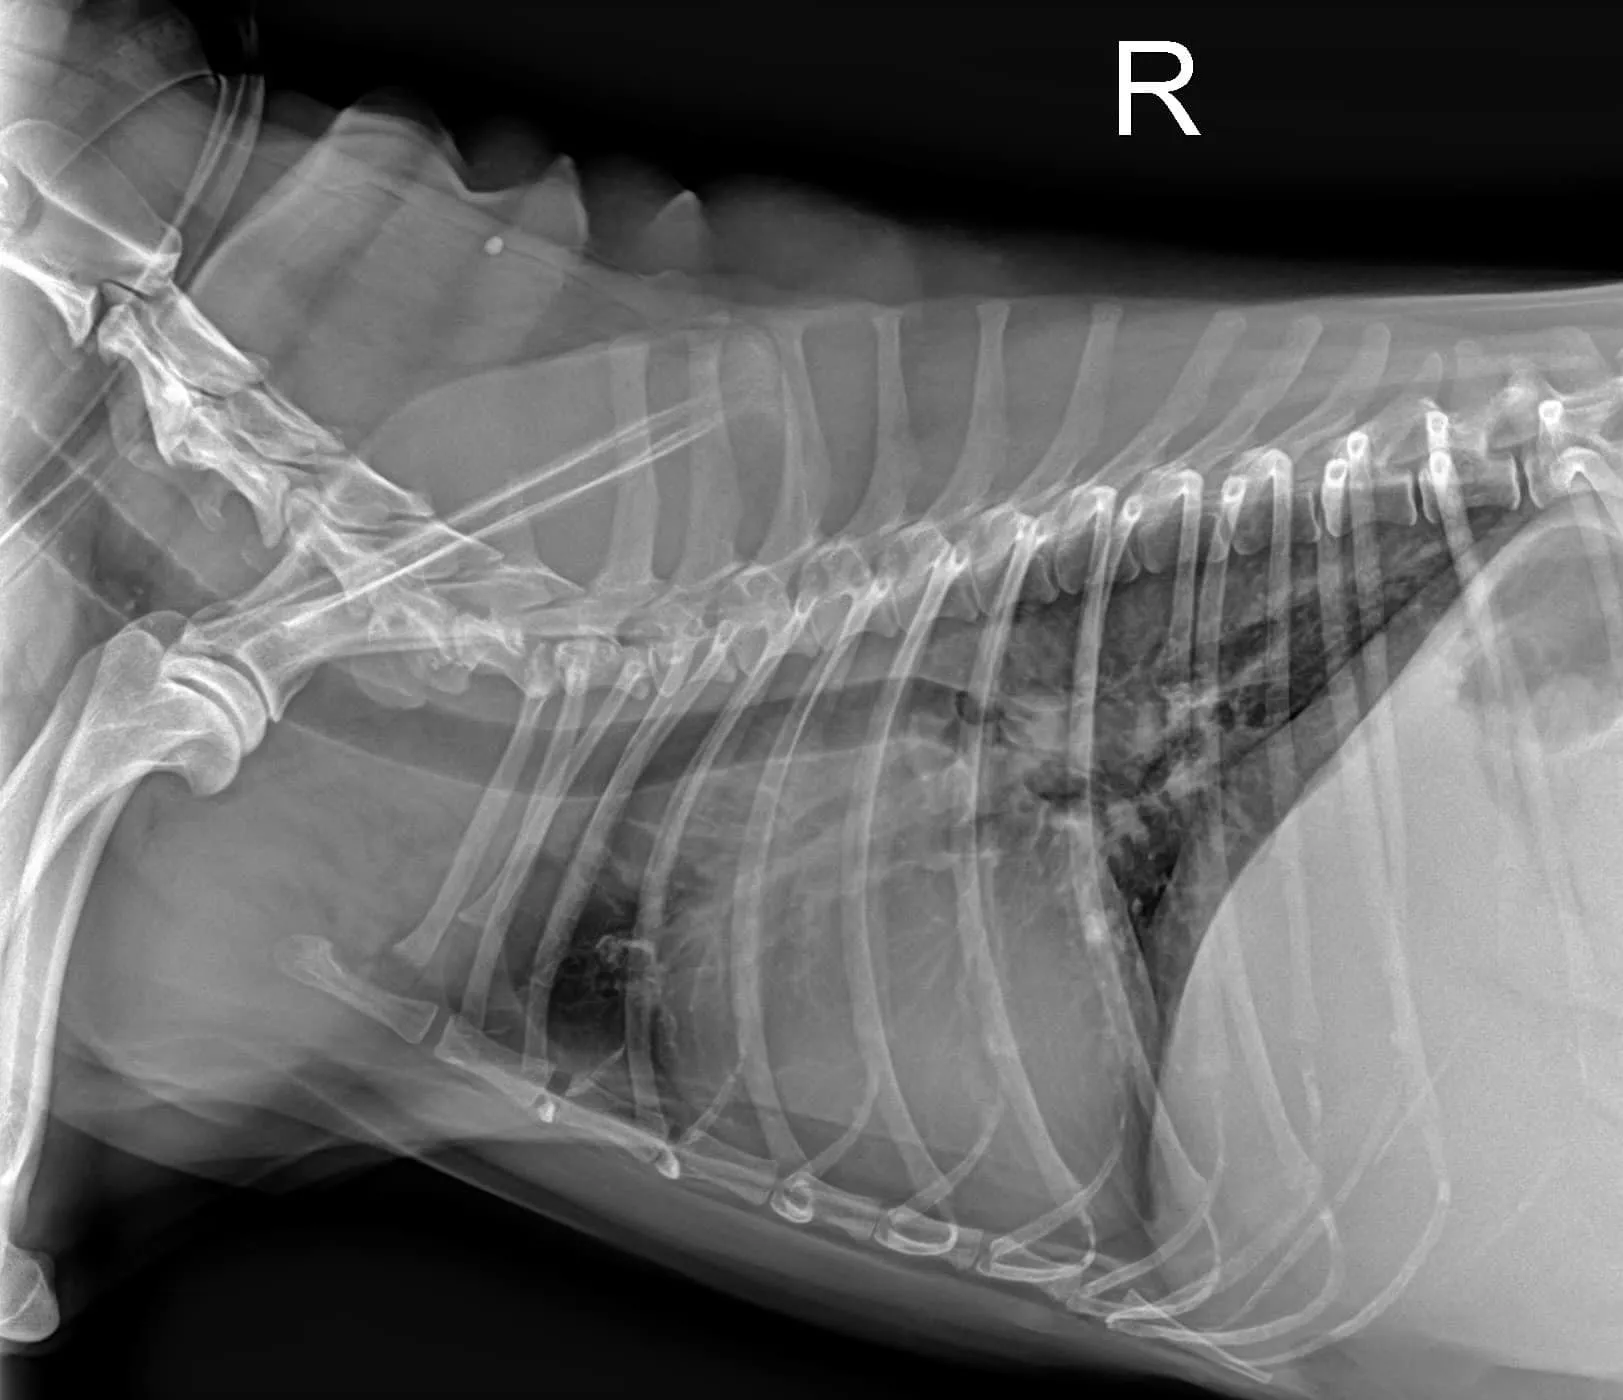

心臟疾病的第二步: 🩻X光檢查

了解毛孩的心臟、肺臟與胸腔的狀況,進一步了解心臟大小與輪廓,並區別肺水腫、胸水或其他問題。

🩻第二步: X光檢查,心臟輪廓變大(VHS=11.0);肺葉呈現肺泡型病徵(alveolar pattern)。

心臟疾病的第二步: 🩻X光檢查

了解毛孩的心臟、肺臟與胸腔的狀況,進一步了解心臟大小與輪廓,並區別肺水腫、胸水或其他問題。

🩻第二步: X光檢查,心臟輪廓變大(VHS=11.0);肺葉呈現肺泡型病徵(alveolar pattern)。